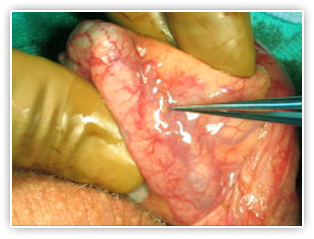

Vasovasostomy

The vasovasostomy is the most commonly performed vasectomy reversal surgery. During a vasovasostomy, the separated ends of the vas deferens are reconnected. See Dr. Bastuba perform a vasovasostomy with these step-by-step reverse vasectomy pictures.